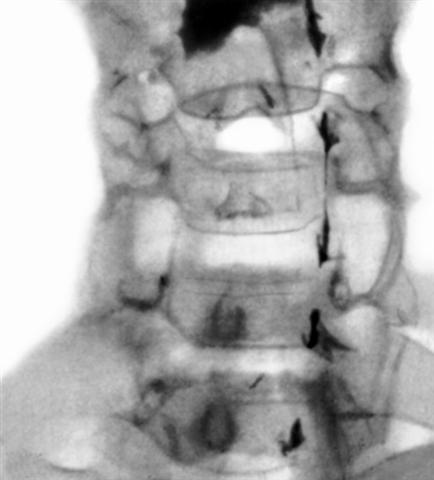

Рис. 6. Миелограмма шейного отдела позвоночника при опухоли, растущей в направлении позвоночного канала: рентгеноконтрастное вещество не проходит ниже уровня четвертого шейного позвонка.